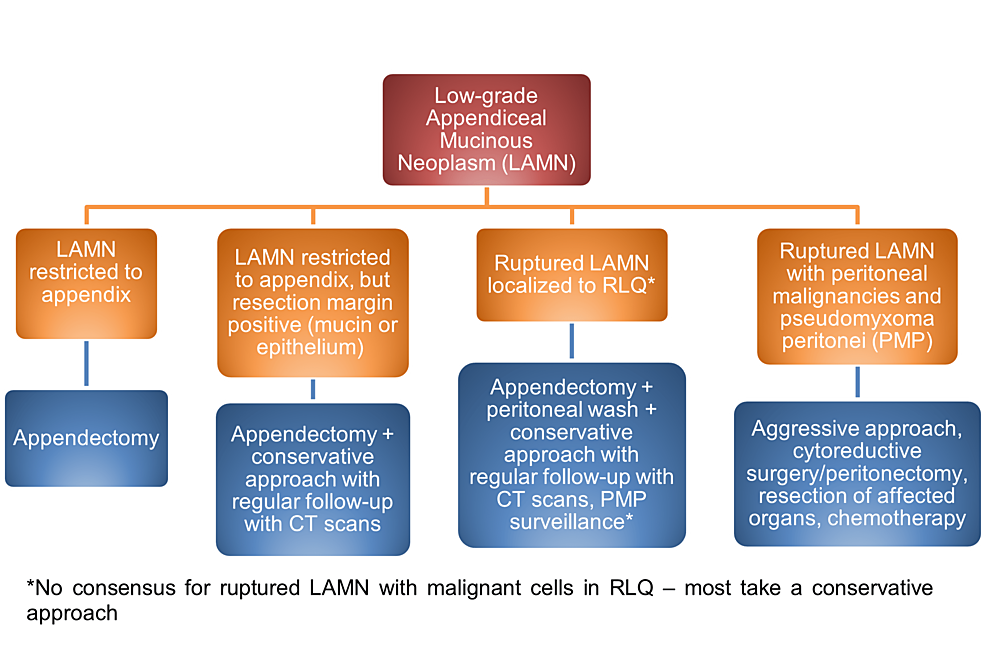

To reduce risks of rupture and PMP progression and examine for the presence of LAMN pathologically, surgical removal of the appendix is crucial for further diagnosis and management [1-3]. Options for removal include open and laparoscopic resection. While open surgery is sometimes recommended to prevent LAMN rupture and PMP, there are documented cases of rupture and PMP in both open and laparoscopic resection with no comparative study available [5]. Including a cuff of the cecum without involving the ileocecal valve is preferred during appendectomy to ensure removal of the lesion [6]. Gross examination shows a cystically dilated mucinous appendix with a hyalinized, thin, fibrotic, or calcified wall and a smooth, corrugated, or granular lining (Figure 1) [1-2]. Because LAMN does not spread via the hematogenous or lymphatic route, an appendectomy is generally acceptable for the management of LAMN confined to the appendix on pathology, with conservative follow-up and surveillance if the appendectomy margins involve acellular mucin or neoplastic epithelium (Figure 5) [2, 7-8]. If acellular mucin is extruded on the appendiceal serosal surface without peritoneal dissemination, an appendectomy with close observation and evaluation for PMP via routine imaging appears to be sufficient [1-2]. Though recommendations on imaging frequency and duration may vary given there are no formal guidelines, we recommend annual CT imaging for five to ten years. Additionally, supplemental right hemicolectomy does not provide advantages over appendectomy in these patients and can involve the retroperitoneum, which may result in the seeding of the mucinous epithelium [2, 8]. If there is peritoneal dissemination, management may require appendectomy, irrigation, a biopsy of peritoneal nodules, peritonectomy, and chemotherapy [3].

Staging is vital to examine for dissemination of mucin and neoplastic cells into the peritoneum and progression to PMP and metastasis. In pTis(LAMN), the LAMN is confined to the appendiceal wall, although acellular mucin or mucinous epithelial cells may still extend into the muscularis propria but not the mesoappendix or serosa [10]. In pT3, LAMN with acellular mucin or mucinous epithelium invades into the subserosa or mesoappendix but not the serosa [10]. In pT4, LAMN with acellular mucin or mucinous epithelium invades into the serosa of the appendix or mesoappendix (pT4a) or directly invades adjacent organs and structures (pT4b) [10]. In M1a, acellular mucin is disseminated intraperitoneally [10]. In M1b, metastasis occurs in the peritoneum [10]. In M1c, metastasis extends beyond the peritoneum [10]. If peritoneal metastasis or PMP is detected, the patient may require cytoreductive surgery (CRS), heated intraperitoneal chemotherapy (HIPEC), or early post-operative intraperitoneal chemotherapy (EPIC) [2,11]. CRS includes peritonectomy and clears away tumor cells to enhance the penetrability of HIPEC and EPIC [2,11]. After CRS and HIPEC, EPIC can be used to augment intraperitoneal therapy against tumor deposits [11].

Low-grade appendiceal mucinous neoplasms are lesions of the appendix that can rupture and lead to PMP, an intraperitoneal dissemination of mucinous ascites and tumors with a high risk of mortality. For LAMN confined to the appendix, appendectomy alone is typically sufficient for management, with conservative follow-up and imaging if the margins involve acellular mucin or neoplastic epithelium. For LAMN with extruded acellular mucin localized to the appendiceal serosa, management is done with appendectomy and PMP surveillance. Peritoneal dissemination should be managed with appendectomy, a biopsy of peritoneal lesions, irrigation, and follow-up evaluation for CRS, HIPEC, and EPIC. With timely workup and management, this may help reduce the risk of complications, improve overall outcome, and increase the chance of survival and recovery.